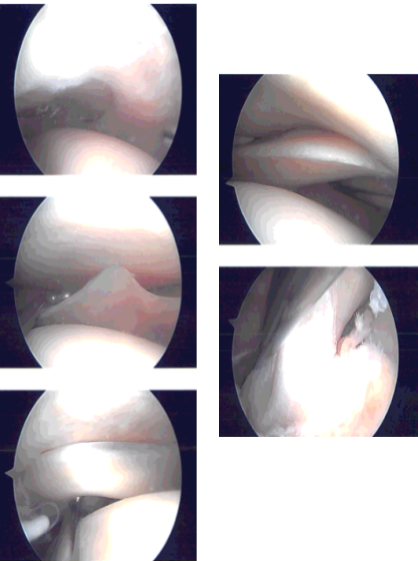

Entry portal was made laterally with a lateral parapatellar incision. Arthroscope was entered. Patellofemoral joint showed no injury. A medial plica could be seen. The scope was entered in the medial tibiofemoral compartment. Medial entry portal was made with the use of a spinal needle.

The medial compartment showed no tear of the medial meniscus. There was no cartilage tear. The scope was entered into an intercondylar notch. The ACL was intact with subtle degeneration.

The scope was entered into the lateral compartment where there was some fraying of the medial margin of lateral meniscus which was cleaned with the use of shaver and biter. No other meniscal tear was found.

Scope was entered into the patellofemoral compartment where there was no cartilage damage though there was patellar maltracking. There was a medial synovial plica which was prominent. It was debrided with the use of a shaver.

Final pictures were taken and saved. The knee was irrigated and drained. Knee was closed with nylon # 3-0. Naropin 9 cc mixed with 40 mg of Depo-Medrol was injected into the knee.

Intraoperative Arthroscopy Images